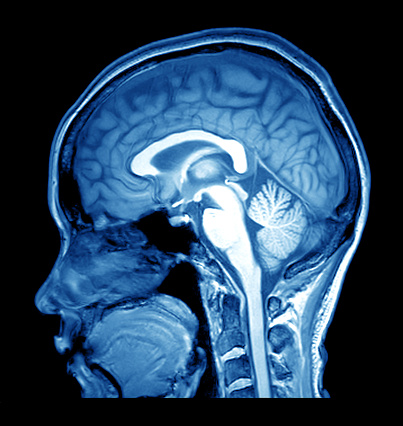

World heart day: Enlarged heart, diabetes and heart disease, fluid around the heart, massive heart attack